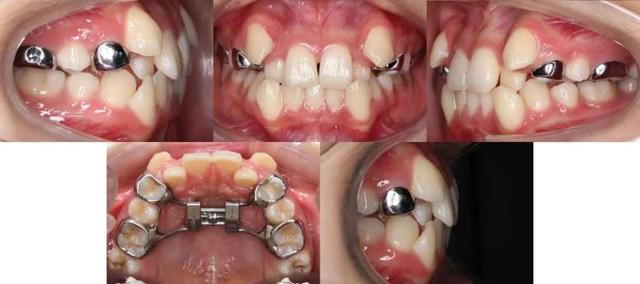

案例:梓豪的牙齿换后歪歪扭扭的,还有点龅牙,很影响美观,妈妈带他来正畸医生这咨询牙齿矫正,被医生告知他的上牙弓发育太窄了,需要扩弓治疗,那什么是牙弓狭窄呢?我们一起来了解一下吧!

这是一种通过粘接在牙齿上固位的固定式扩弓方式。通过扩弓能够有效地打开腭中缝,随后腭中缝会被新生骨慢慢填满,它适用恒双尖牙已萌出的青少年。